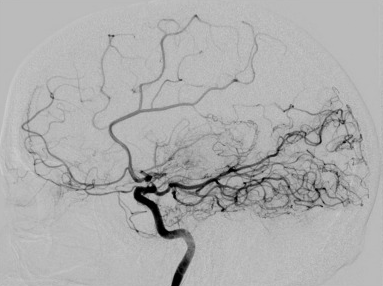

중풍이라고도 불리는 뇌졸증은 뇌의 일부 혹은 전체에 기능적 이상이 발생하여 그 상태가 상당 기간 지속되는 것을 말하며, 뇌출혈이나 뇌경색으로 인해 발생한다. 이러한 뇌졸증은 주로 고혈압이나 당뇨, 고지혈증 등의 만성적인 혈관 질환을 앓고 있는 노인에게 흔한 병으로 알려져 있다. 소아청소년에서 뇌졸증이 발생하는 경우는 매우 드물지만, 그 중 많은 원인은 모야모야병(Moyamoya disease)이라는 질환 때문인 경우가 많다. 모야모야병은 뇌에 혈류를 공급하는 동맥이 서서히 막히면서 간헐적으로 뇌허혈 증상이 나타나고, 심하면 뇌경색으로 진행되는 뇌혈관 질환이다. 뇌로 가는 동맥 혈관벽이 두꺼워지고 막히면서 보상 작용으로 주변에 곁혈관들이 생기게 되고, 혈관조형술을 통한 영상 검사에서 곁혈관들의 모습이 마치 연기가 모락모락 피어오르는 것 같이 생겼다는 뜻으로 '모야모야' 라고 일본의 스즈키 교수에 의해 명명되었다. 주로 일본, 한국, 몽골 등의 몽고 민족의 아이들에게 호발하는 희귀 난치성 질환이다.

정확한 원인은 알 수 없으나 17번 염색체에 위치한 RNF 유전자와 연관이 있는 것으로 여겨지며, 10~15% 정도 가족력이 있다. 다운증후군, 신경섬유종증, 결절성경화증, 겸상 적혈구 빈혈, 판코니 빈혈 등의 질환과 동반되는 경우에는 모야모야 증후군이라고 불리운다. 성인에서도 발생 가능하며 주로 30~50세에서 뇌출혈과 동반되는 경우가 많고, 소아는 주로 5~10세에서 발병한다. 진단을 위해서는 자기공명혈관조영술(MRA, MRI 기계를 이용하여 혈관이 잘 보이는 영상을 얻는 것)을 이용해 특징적인 곁혈관들의 모습을 확인할 수 있다. 더욱 정확하게 병변을 확인하고 구체적인 수술 계획을 위해서는 도관을 이용한 혈관조영술을 시행한다.